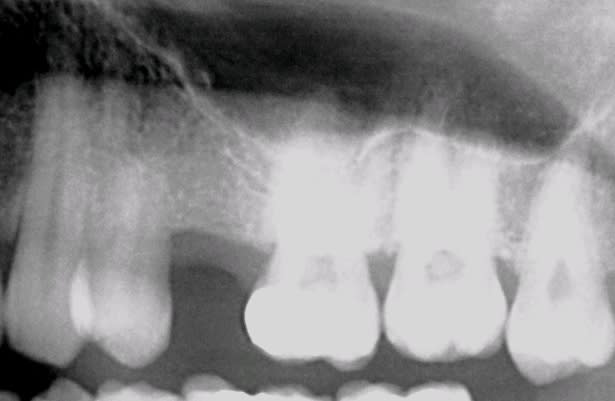

un p'tit Summers du samedi matin: sur le cliché post op on distingue le fragment de corticale qui a sauté avec le premier ostéotome.

(implant tekka progress 4.5 13, os autogène récupéré lors du forage)